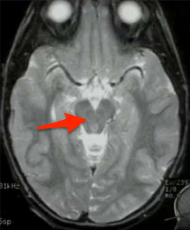

What structure is indicated below?

Midbrain. Note that it looks like Mickey Mouse w/ his hears being the cerebral peduncles.